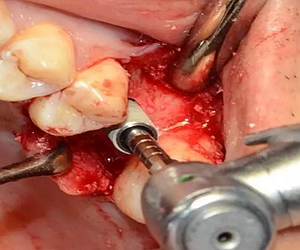

植入種植體,注意方向控制和初期穩(wěn)定性。

上覆蓋螺絲